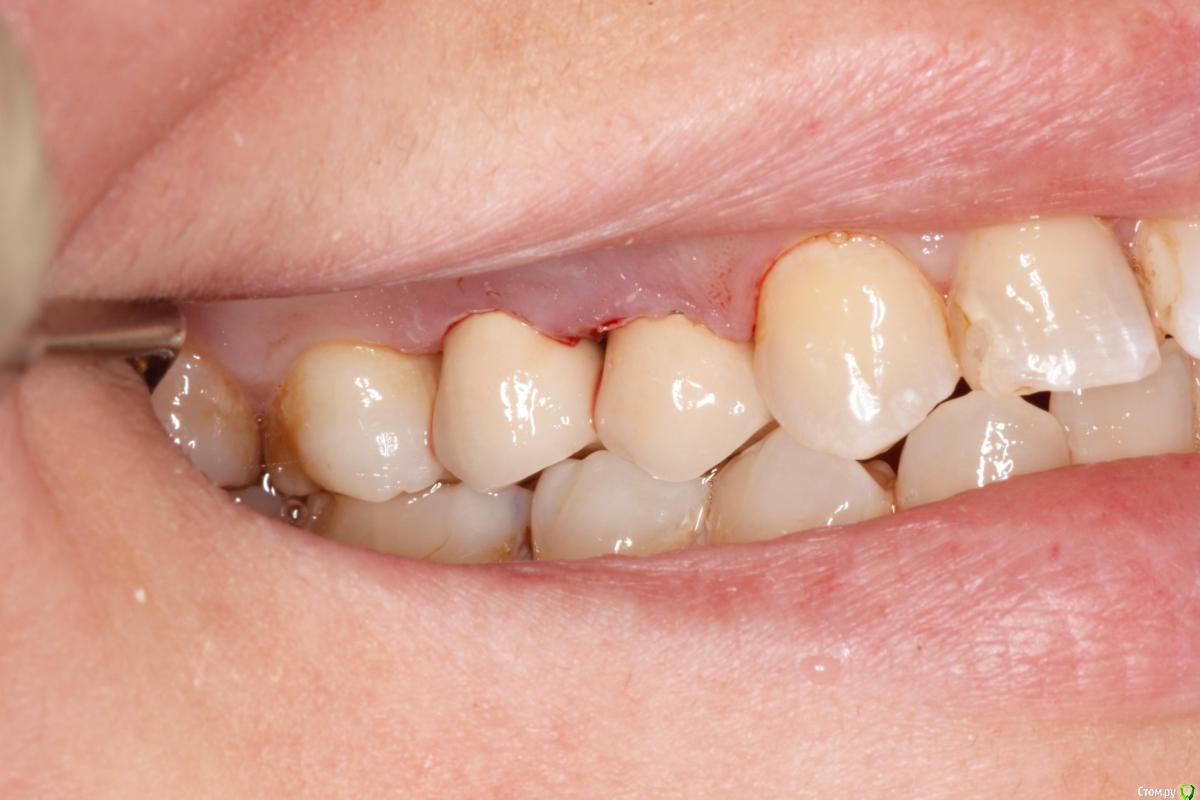

skeettrap Опубликовано 5 июля, 2016 Поделиться Опубликовано 5 июля, 2016 Стандартная ситуация : коллега попросила сделать родственнице (мужа) за неделю - во время краткосрочного визита из Израиля.Исходная ситуация 14,15 сильно разрушены с временными пломбами и наплывшей десной(фото не сделал).На первом этапе сделаны культевые вкладки прямым методом (десну подрезал бором). Постановка вкладок на следующий день, изготовление временных коронок, снятие слепков. Через 2 дня - фиксация. Ссылка на комментарий

skeettrap Опубликовано 6 июля, 2016 Автор Поделиться Опубликовано 6 июля, 2016 На удлинение времени не было. Главное было проснять. Временные делаю так: после замешивания немного жду, когда начинает полимеризоваться, делаю типа брусочка, даю накусить, немного с боков приминаем (это при открытом рте). До окончательного отверждения несколько раз вынимаю и вставляю. По мере нагрева помещаю в холодную воду.После отверждения формирую предварительно, внутри немного убираю и делаю перебазировку. Окончательно формирую и фиксирую. Ссылка на комментарий